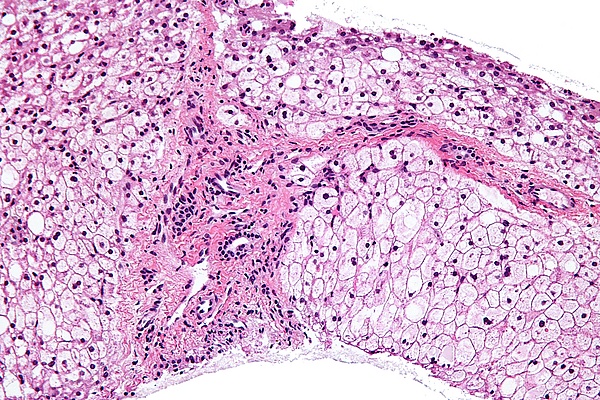

Болезнь сопровождается отложением атипичного гликогена в печени, сердце, мышцах.